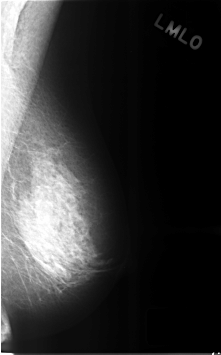

C_0315_1.LEFT_MLO

LEFT_MLO LINES 4608 PIXELS_PER_LINE 2864 BITS_PER_PIXEL 12 RESOLUTION 50 NON_OVERLAY